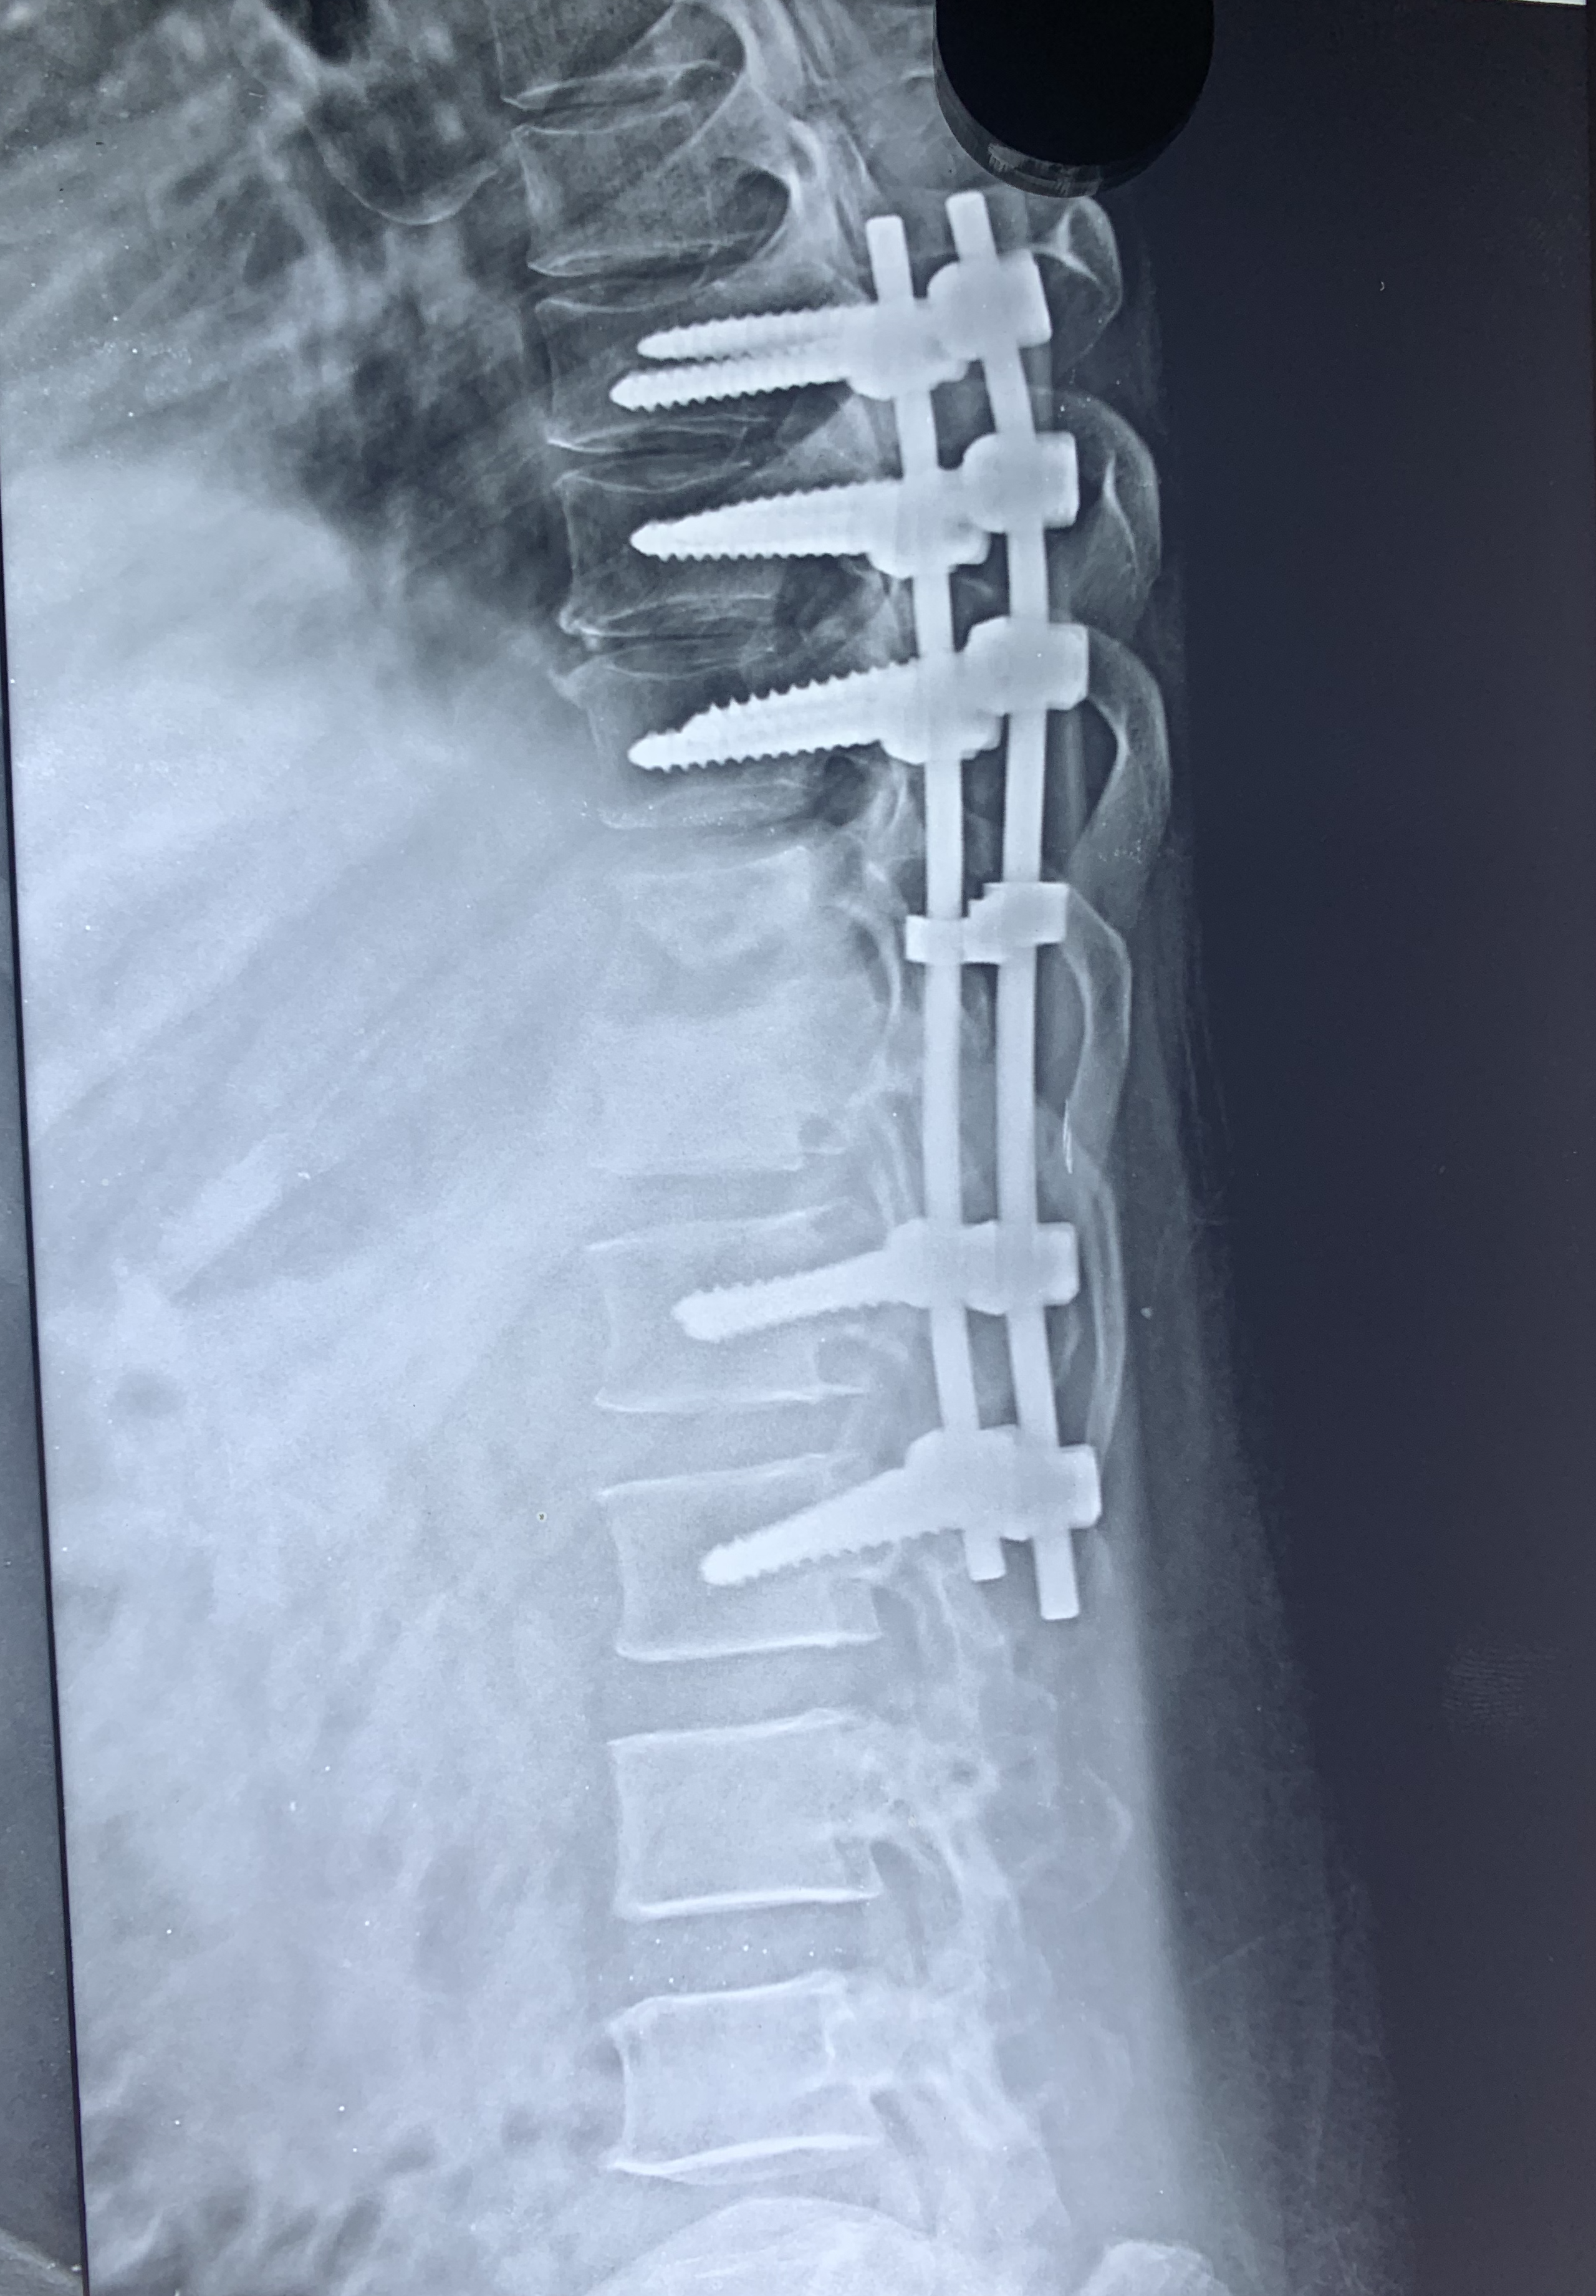

PROFILE TRAINING AND PRESENTATION Dr. Niranjanan Recieving Diploma SICOT degree in Rome, Italy Dr. Niranjanan being awarded fellowship certificate at Indian spinal injuries centre CLIINIC SOME OF Dr. NIRANJANAN's CASES